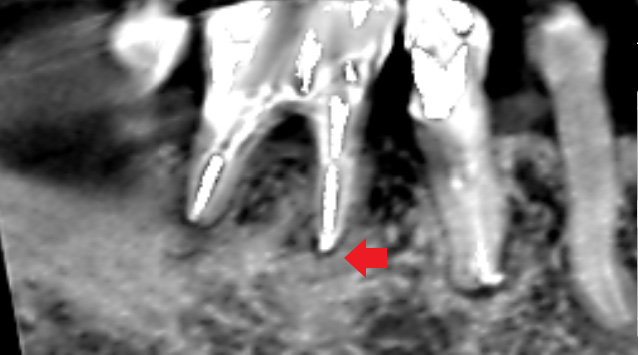

下の画像は、根管治療されていた大臼歯の初診時のCT画像です。根の先には根尖病変の炎症像は特にみられませんでした。他の歯の治療後の経過観察中に膿ができてきたケースです。根管治療が必要になったので、通法通り再根管治療を行い、膿は改善しました。

最初に膿が見あれなくても、後から膿んでくることもあるので、根管治療をしてあって膿がみられなかったケースでも、被せ直しをする際には、事前に再根管治療をしておいた方が良いです。

特に、被せ直しをする歯は、最初に膿がみられなくても後から膿んでくることがあるので、予防的に根管治療をやり直しておいた方が無難です。当医院では、すでに根管治療されている歯の被せ直しをする場合は、膿がみられなくてもあとで困らないように根管治療のやり直しを必ずするようにしています。